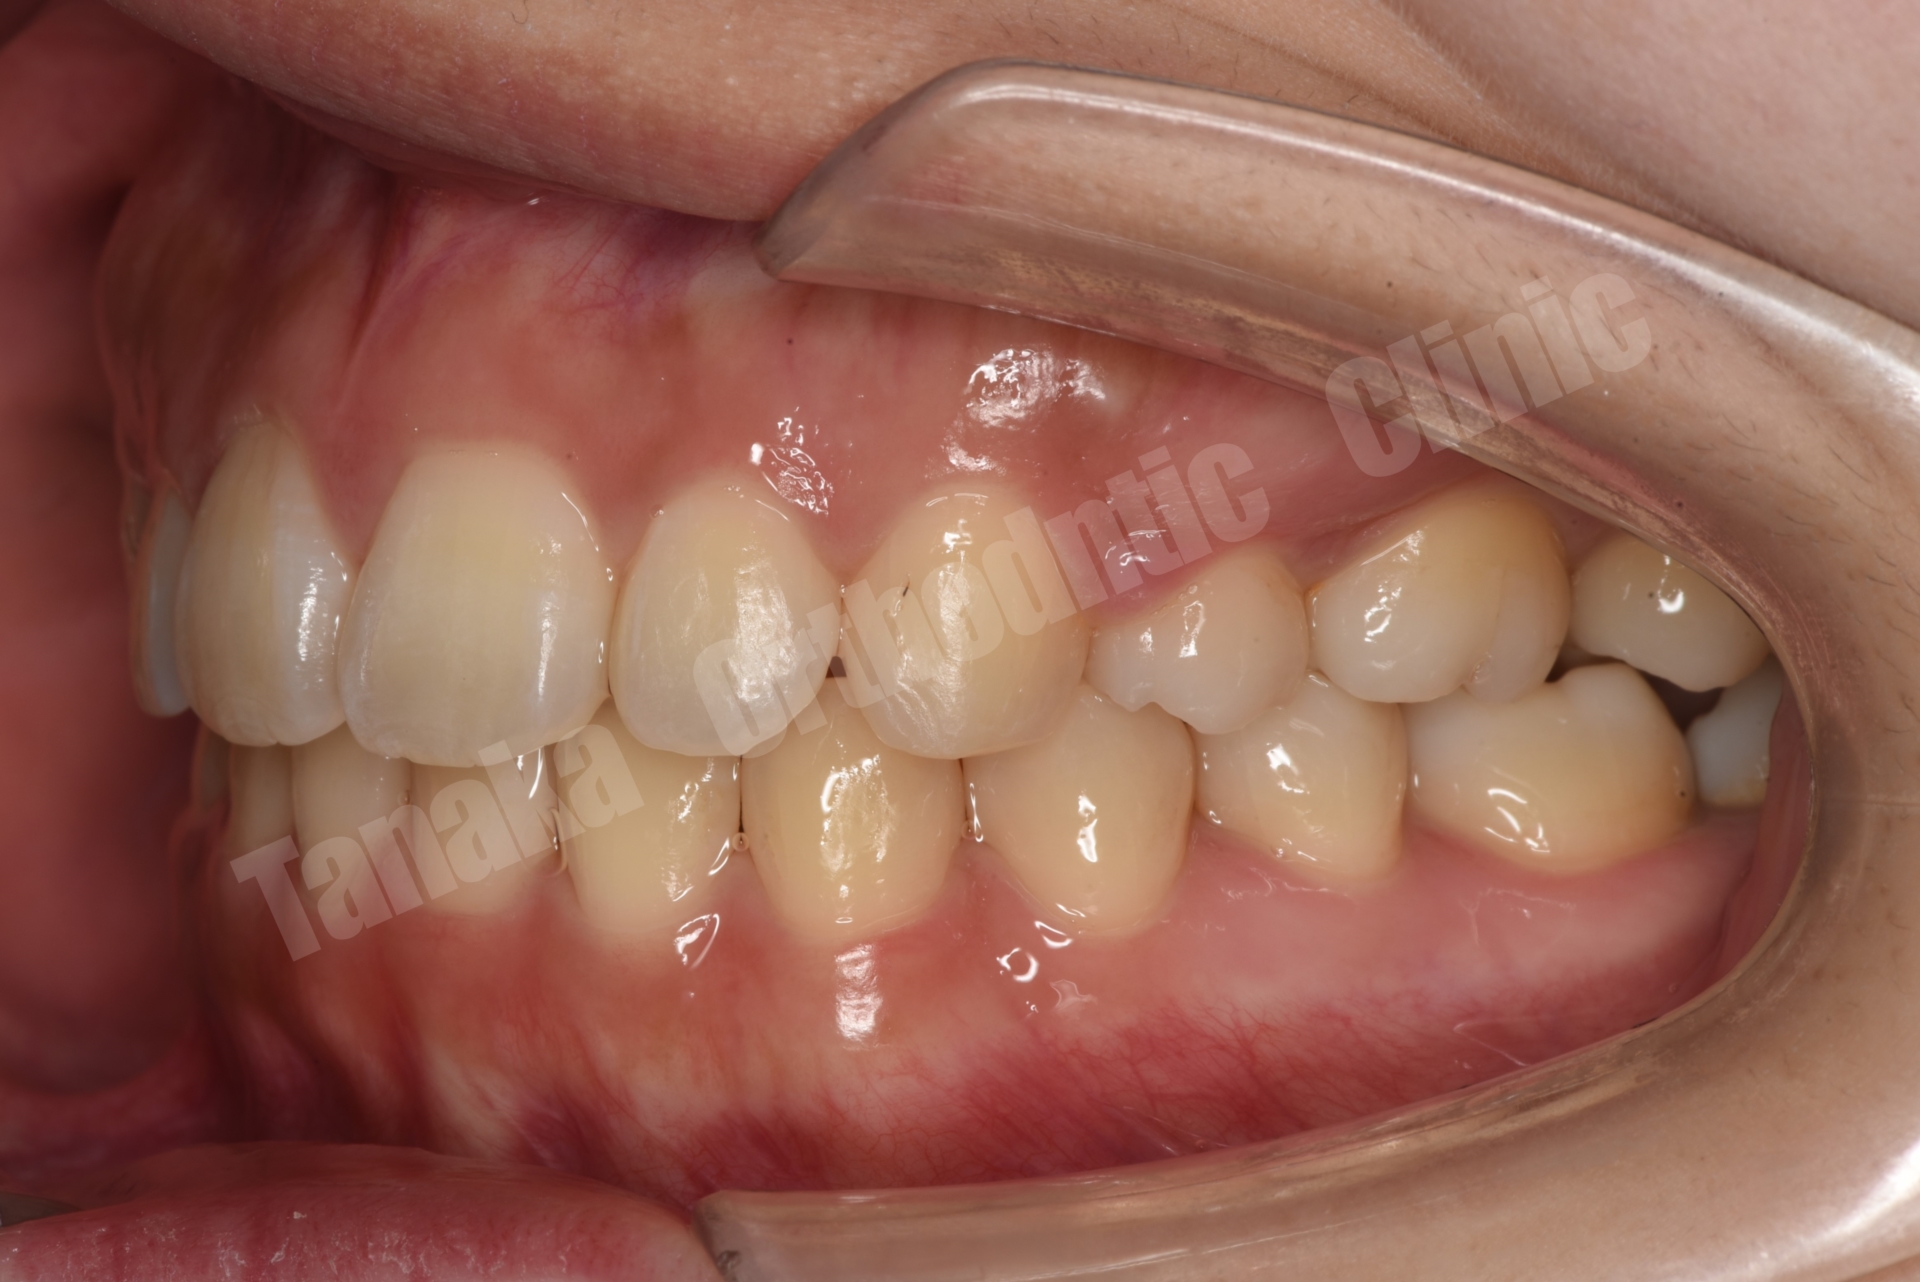

結果として歯の移動は順調に進み、約1年8か月で治療を終了することができました。気になっていた上顎前歯の突出感と側貌は改善し、前歯の咬み合わせも回復しました。また右下乳臼歯部のスペースを閉鎖することで、将来的にインプラントなどの補綴処置が必要になる可能性も回避することができました。